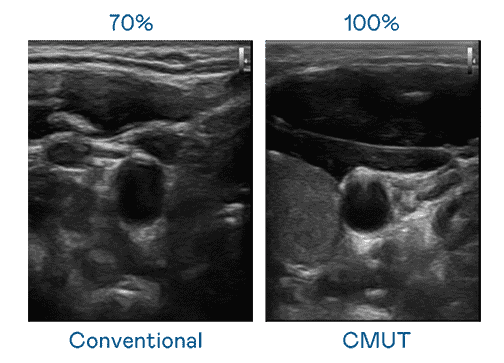

CMUT 技术是一种用电容式微机电元件来产生超音波讯号的技术。。与传统 PZT 压电式技术相比,,,CMUT 频宽增加 30%,,,更宽频的超音波讯号让影像解析度大幅提升,,是实现高影像品质医疗超音波扫描、、促进精准医疗发展的关键技术。。。

大频宽带来超清晰影像

超音波影像的解析度高低,,,首先取决于探头能发出的讯号频宽。。。。牛牛游戏 CMUT 可提供高清晰的超音波讯号,,,,提供高频宽、、、、高灵敏度、、、、影像纹理细节更高的超音波影像,,协助医护人员缩短影像判读时间及利用精准的医疗影像进行诊断。。。